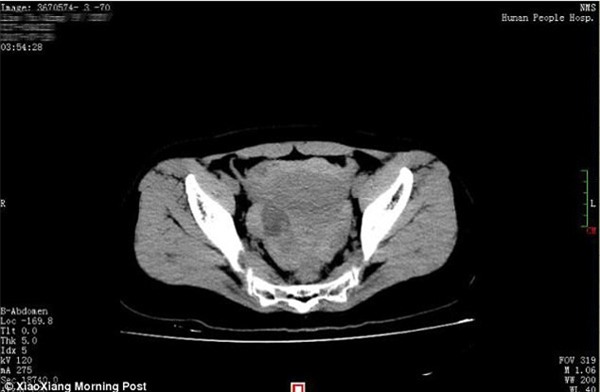

Hình ảnh scan của Xiao Qing cho thấy xuất huyết máu ồ ạt trong vùng khoang xương chậu.

Bác sĩ Huang Mei nói với phóng viên rằng Xiao Qing không có bầu nhưng có một lượng chất dịch và máu lớn trong vùng bụng và vùng chậu theo kết quả chụp CT.

Bác sỹ Mei đã lập tức tiến hành nội soi bụng chẩn đoán cho Xiao, kết quả cho thấy Xiao có máu trong khoang phúc mạc.

"Có khoảng 1.500ml máu bị mất từ phần bụng của bệnh nhân, chiếm khoảng 40% lượng máu của cô. Nếu tới bệnh viện trễ hơn, tính mạng của bệnh nhân có thể đã bị đe dọa", bác sỹ nhấn mạnh.

Các bác sĩ cũng tìm thấy một nang buồng trứng đường kính 3 cm bị vỡ bên buồng trứng phải của Xiao Qing. Đây chỉ là một u nang lành. Cô đã trải qua phẫu thuật cắt bỏ u nang.